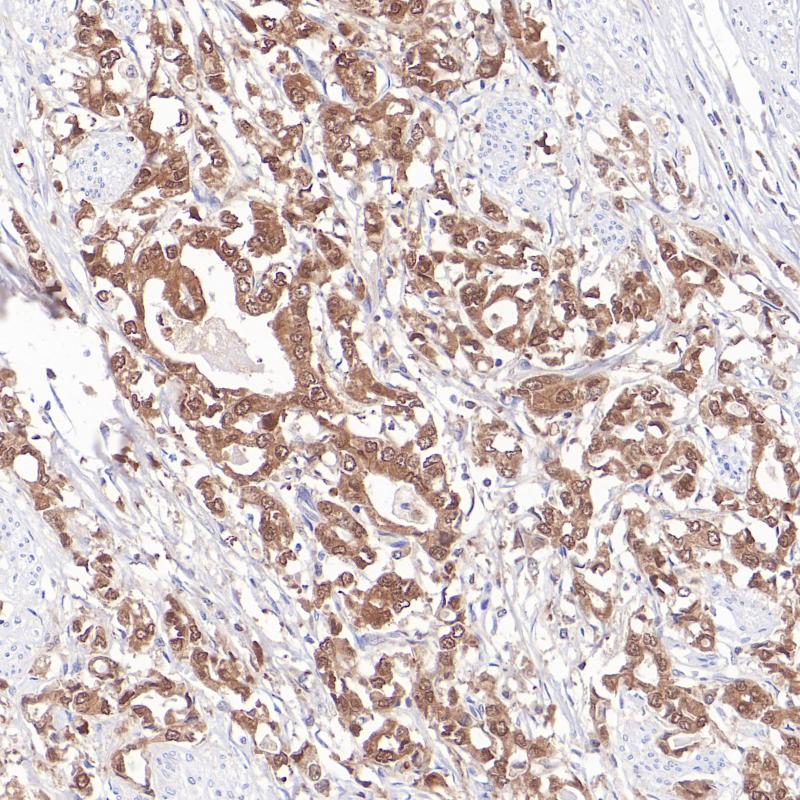

SOX10 重组兔单克隆抗体

阳性对照

黑色素瘤

亚细胞定位

细胞核